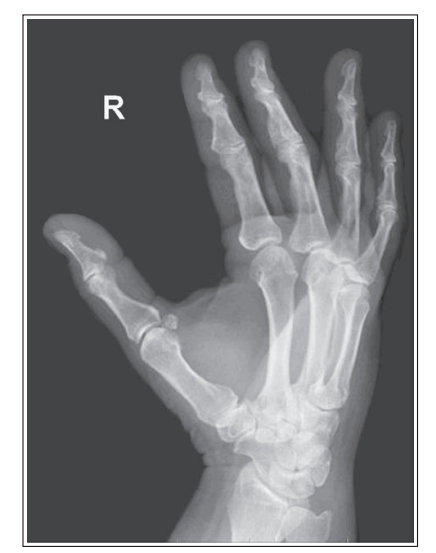

2nd metacarpal is in profile

Slight internal rotation